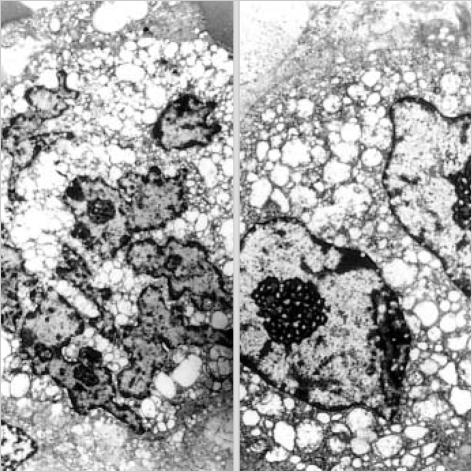

Osteoclast-like giant cell tumor of the pancreas is a very rare neoplasm, of which the histiogenesis remains controversial. A 63-yr-old woman was hospitalized for evaluation of epigastric pain. An abdominal computerized tomography revealed the presence of a large cystic mass, arising from the tail of pancreas. A distal pancreatectomy with splenectomy was performed. Histologically, the tumor was composed of mononuclear stromal cells intermingled with osteclast-like giant cells. In addition, there was a small area of moderately to well differentiated ductal adenocarcinoma. The final pathologic diagnosis was osteoclast-like giant cell tumor of the pancreas with ductal adenocarcinoma. Here, we describe the histopathological, immunohistochemical, ultrastructural and molecular biological findings of this tumor with review of the literature pertaining to this condition.

胰腺破骨细胞样巨细胞瘤是一种非常罕见的肿瘤,其组织发生仍存在争议。一名63岁女性因上腹部疼痛入院评估。腹部计算机断层扫描显示胰腺尾部有一个大的囊性肿块。行远端胰腺切除术加脾切除术。组织学上,肿瘤由单核基质细胞与破骨细胞样巨细胞混合组成。此外,还有一小片中度至高分化的导管腺癌区域。最终病理诊断为胰腺破骨细胞样巨细胞瘤合并导管腺癌。在此,我们描述了该肿瘤的组织病理学、免疫组织化学、超微结构和分子生物学发现,并回顾了有关这种情况的文献。